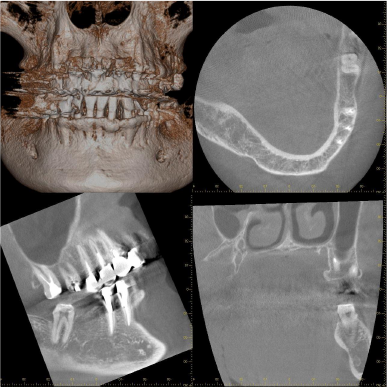

デンタルおよびCT所見

before before |

after after |

術前 術前 |

術後8カ月 術後8カ月 |

歯周病により失われた歯槽骨が骨様組織により改善されているように思われます。

レントゲン写真では矢印の位置ぐらいには骨がありそうに見えますが、CTにて詳しく調べてみると矢印の位置まで歯周病が進行して骨が破壊されていることがわかります。

患者さんと相談した結果、歯周組織再生療法を希望されたため、施術させていただくことになりました。

術直後のレントゲン写真です。

術前で破壊されていた部分に骨の再生が認められるため、黒かった部分が白くなっていることがわかります。